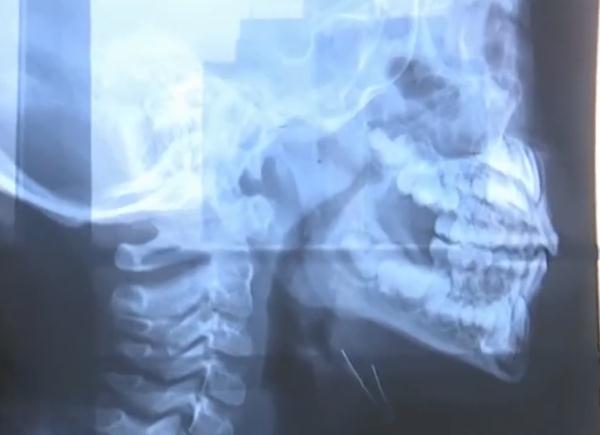

這名男孩是腺樣體肥大導(dǎo)致鼻子不通氣

自己的孫女剛做完腺樣體肥大手術(shù)

檢查后是因為腺樣體肥大

兒童腺樣體肥大導(dǎo)致口呼吸癥狀

一般來說腺樣體肥大超過三分之二

會影響孩子鼻呼吸

建議手術(shù)調(diào)節(jié)